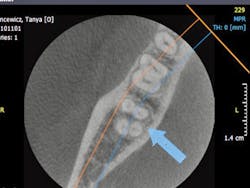

General dentists accomplish the vast majority of endodontic treatment in the United States. This treatment is reported to be the third most frequent use of cone beam. Endodontists, who are the leaders and teachers for endodontic treatment, are now using cone beam routinely. What are some of the reasons for this use? All of us occasionally have a patient with an endodontically treated tooth that appears on a 2-D radiograph to have received excellent endodontic treatment, but the patient still has discomfort. You know the various potential reasons for this treatment failure, but can you visually determine them? Is the tooth cracked? Is there another root or another canal that you cannot see on a 2-D image? Do overlapping roots disguise a problem or condition that could easily be seen on a 3-D image (figures 4-6)? It is easy to predict that cone beam will soon become recognized as being necessary for predictable endodontic diagnosis and treatment.

Figures 4-6: These images provided by Dale Miles, DDS, MS, show a lower right second molar with multiple roots. It is apparent that a 2-D view would be inadequate to provide enough information for appropriate endodontic treatment.